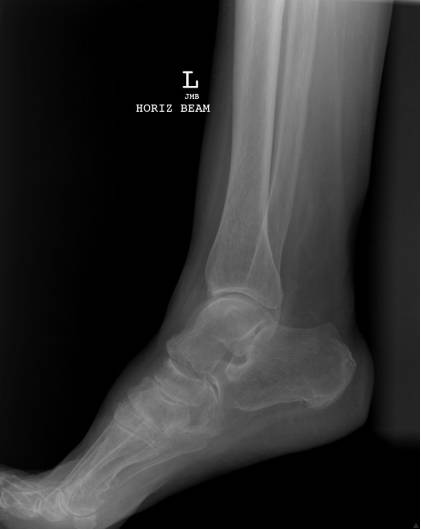

Maisonneuve骨折

由外旋暴力导致的腓骨近端骨折, 常常合并下胫腓分离、内踝骨折、三角韧带撕裂、前距腓韧带断裂、骨间韧带损伤、下胫腓韧带撕裂、后踝骨折等损伤,属于旋前-外旋三度损伤,踝关节不稳定。